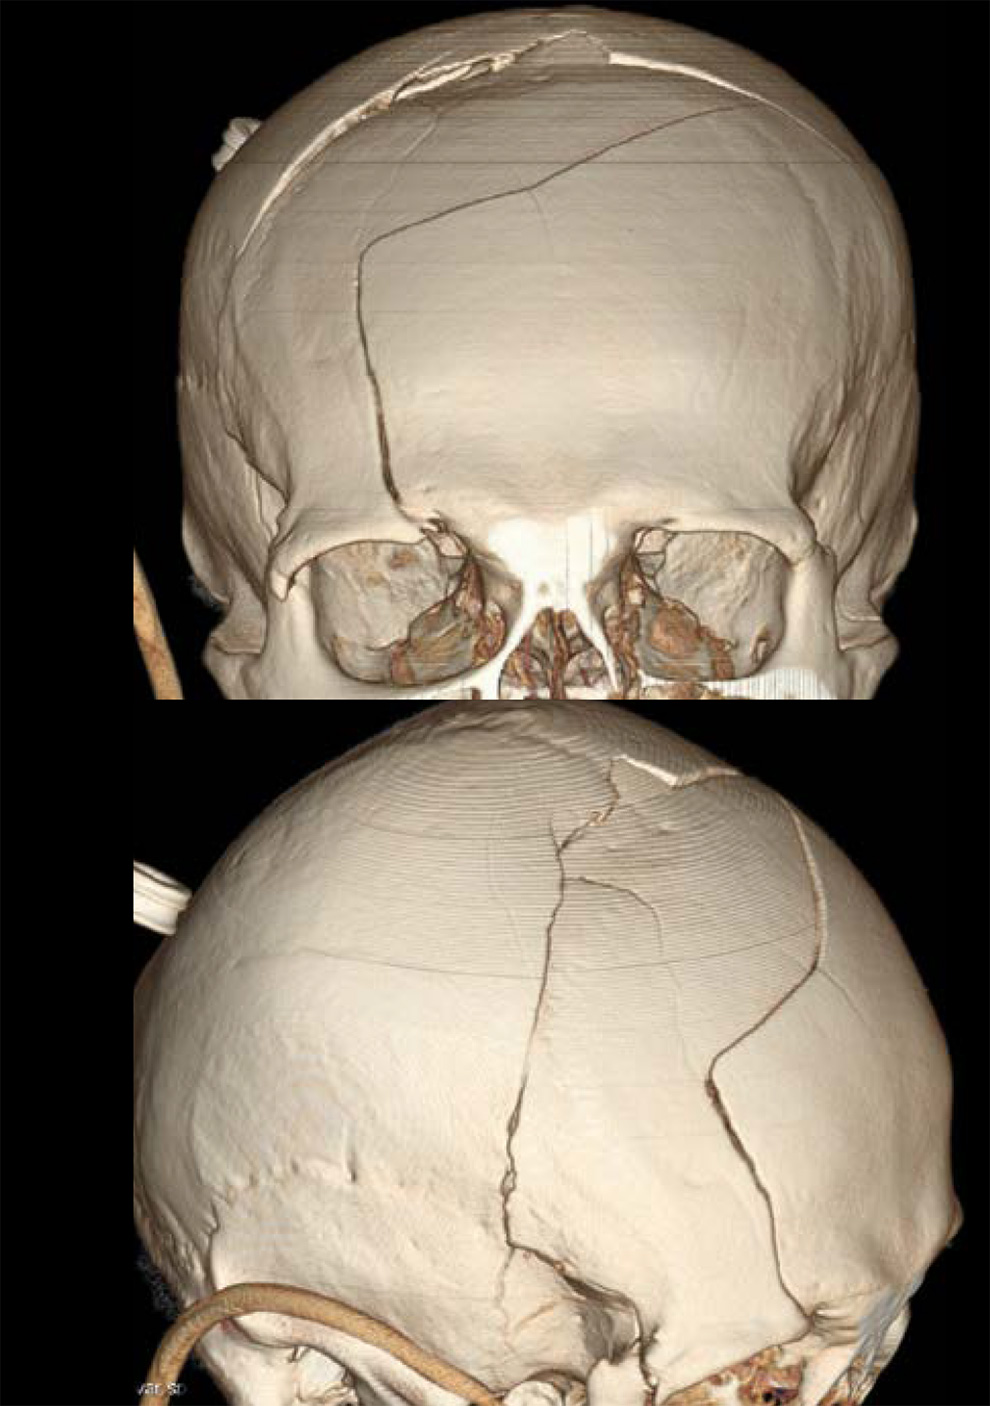

На снимке по МСКТ костей черепа в 3D-реконструкции определяются многооскольчатые переломы лобной кости, теменных костей